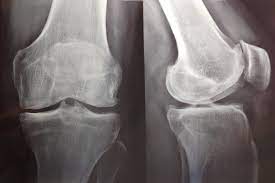

Consumo de opiáceos entre pacientes con artrosis grave de rodilla

En este estudio de utilización de medicamentos se encontró que entre los pacientes daneses con artrosis de rodilla grave, la prevalencia y el uso total de opioides se duplicó durante los 5 años anteriores a al reemplazo de rodilla. Además, el 10% de la población de estudio fue responsable del 90% de los opioides utilizados. Eur J Clin Pharmacol, 13 de junio de 2022